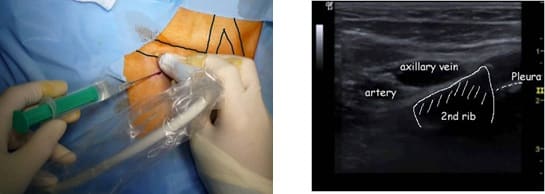

3. Acceso por la vena subclavia en adultos

La vía subclavia en comparación la vía yugular es más funcional y estética evitando muchas de las complicaciones relacionadas con la punción a ciegas.

Además, no es necesario tunelizar, es un abordaje más cómodo et rápido.

Hoy en día, nuestra vía de abordaje de elección era la vena subclavia en el surco deltopectoral, lo cual permite una gran discreción para los pacientes (respeto del escote). Colocamos el 99% de nuestros puertos con este abordaje.

Se punciona la vena en el fondo del bolsillo: de esta manera el catéter tiene un recorrido más fisiológico y evitamos los posibles curvas o acodamientos que pueden crearse cuando la vena se punciona desde otro lugar.